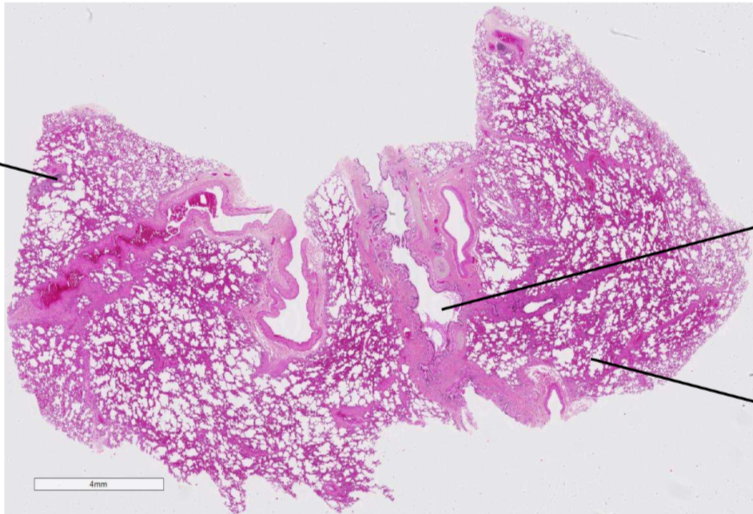

dans la lame suivante , décrit c’est quoi et comment on différencie les structures

il sagit de la lame du poumon

à droite, c’est des bronchioles qu’on peut différencier parceque c’est cilié et pas de cartilage hyalin

à gauche en haut, c’est une bronche ultra pulmo (on le sait parce que petites plaques blanhes de cartilage)

à gauche en bas, c’est le parenchyme pulmonaire qui contient beaucuop d’alvéole